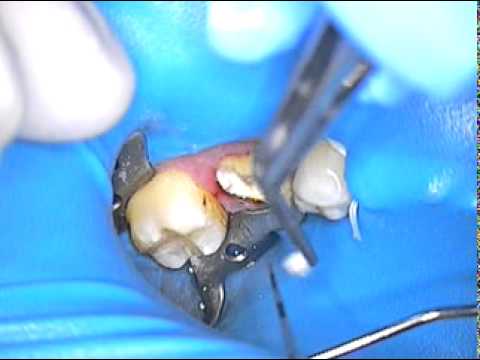

DR. GERARD CUOMO – Root Canal Post Removal 2 | Temporary | Crown | Boca Raton | Florida